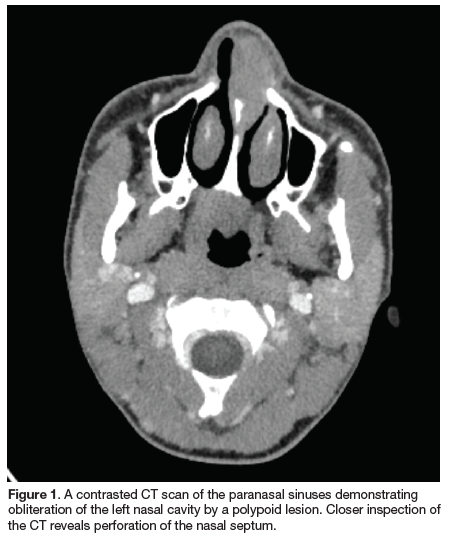

A contrasted CT scan of the paranasal sinuses revealed a soft tissue mass centred in the left anterior nasal cavity, involving the left inferior turbinate and causing saucerisation of the frontal process of the maxilla, maxillary spine and perpendicular ethmoid plate. Importantly, there was no extension of the mass into the maxillary or ethmoid sinuses (Figure 1). The main clinical differential considerations included pyogenic granuloma, nasal polyp and juvenile angiofibroma.

An incisional biopsy of a representative area was performed under local anaesthesia and the specimen was submitted for histological evaluation. Gross examination revealed a 2.2 x 0.8 x 0.3cm polyp with surface ulceration. Microscopically, the polyp was surfaced by a metaplastic squamous epithelium. The subepithelial connective tissue exhibited a dense nonspecific lymphoplasmacytic infiltrate with scattered vague granulomas, consisting of epithelioid histiocytes. Focally, a necrotic background was seen with occasional eosinophils (Figures 2 and 3). Special stains, PAS+D and Methanamine silver were negative for fungi, while Zheel Nielsen (ZN) and Fite were negative for mycobacteria. The plasma cells were strongly immunoreactive for CD138 (Syndecan-1) and PLA (VS38c). Kappa and Lambda in situ hybridisation showed a polycolonal population of plasma cells. CD 56 IHC and EBER in situ hybridisation were negative. Treponema pallidum IHC was positive for spirochetes. The spirochetes were predominantly intraepithelial (epitheliotrophic) with scattered stromal organisms (Figure 4). Based on the histological and immunohistochemical features, a diagnosis of nasal treponematosis was made. The differential diagnosis included sexually transmitted syphilis and endemic syphilis. Due to the relatively young age of the patient at presentation, the possibility of endemic syphilis was favoured. Serological tests, Venereal Disease Research Laboratory (VDRL) and HIV were recommended. However, the patient was subsequently lost to follow-up. Closer inspection of CT images revealed perforation of the nasal septum (Figure 1).